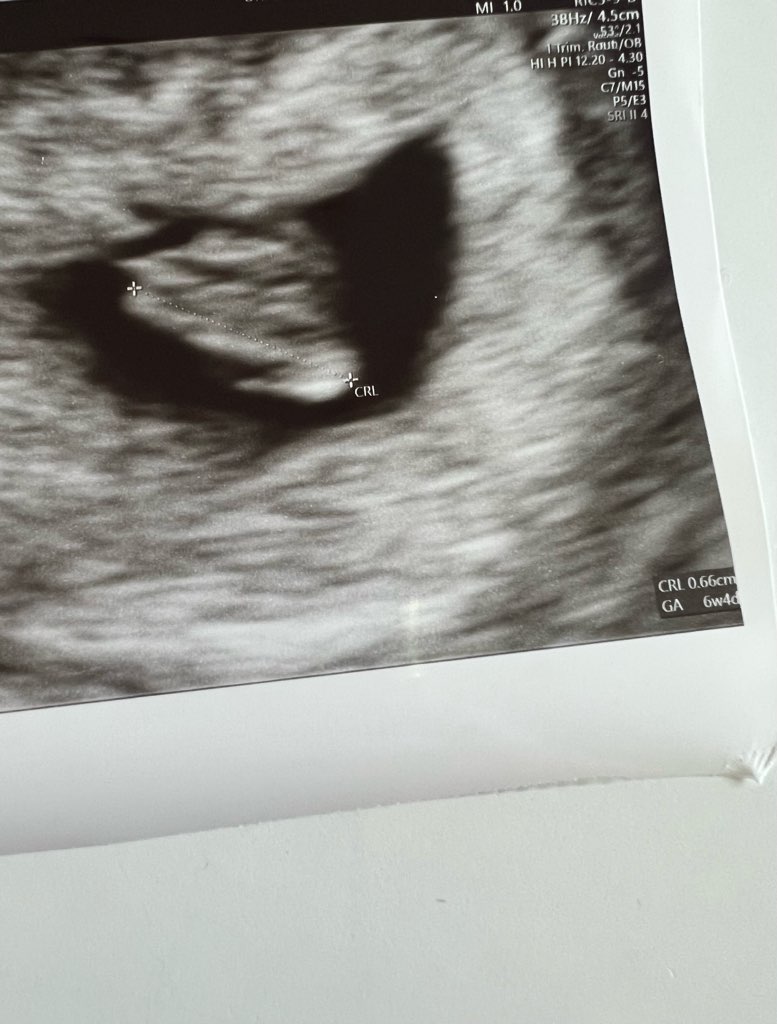

Ja już po ✊🏻 Fasolka urosła od piątku z 1,3mm na 6,6mm 🥹 Udało się oznaczyć serduszko - tętno 119 😍 Lekarz powiedział, że norma jest od 110 do 160, więc ciągle w normie i że to jedyna kwestia do której mógłby się przyczepić, ale że sprawdzimy jak będzie następnym razem. Pęcherzyk „książkowy” 😍✊🏻 Następna wizyta 03.08 i prenatalne mam umówić na 01.09 🙂

I moja fasoleczka 🥹🥹